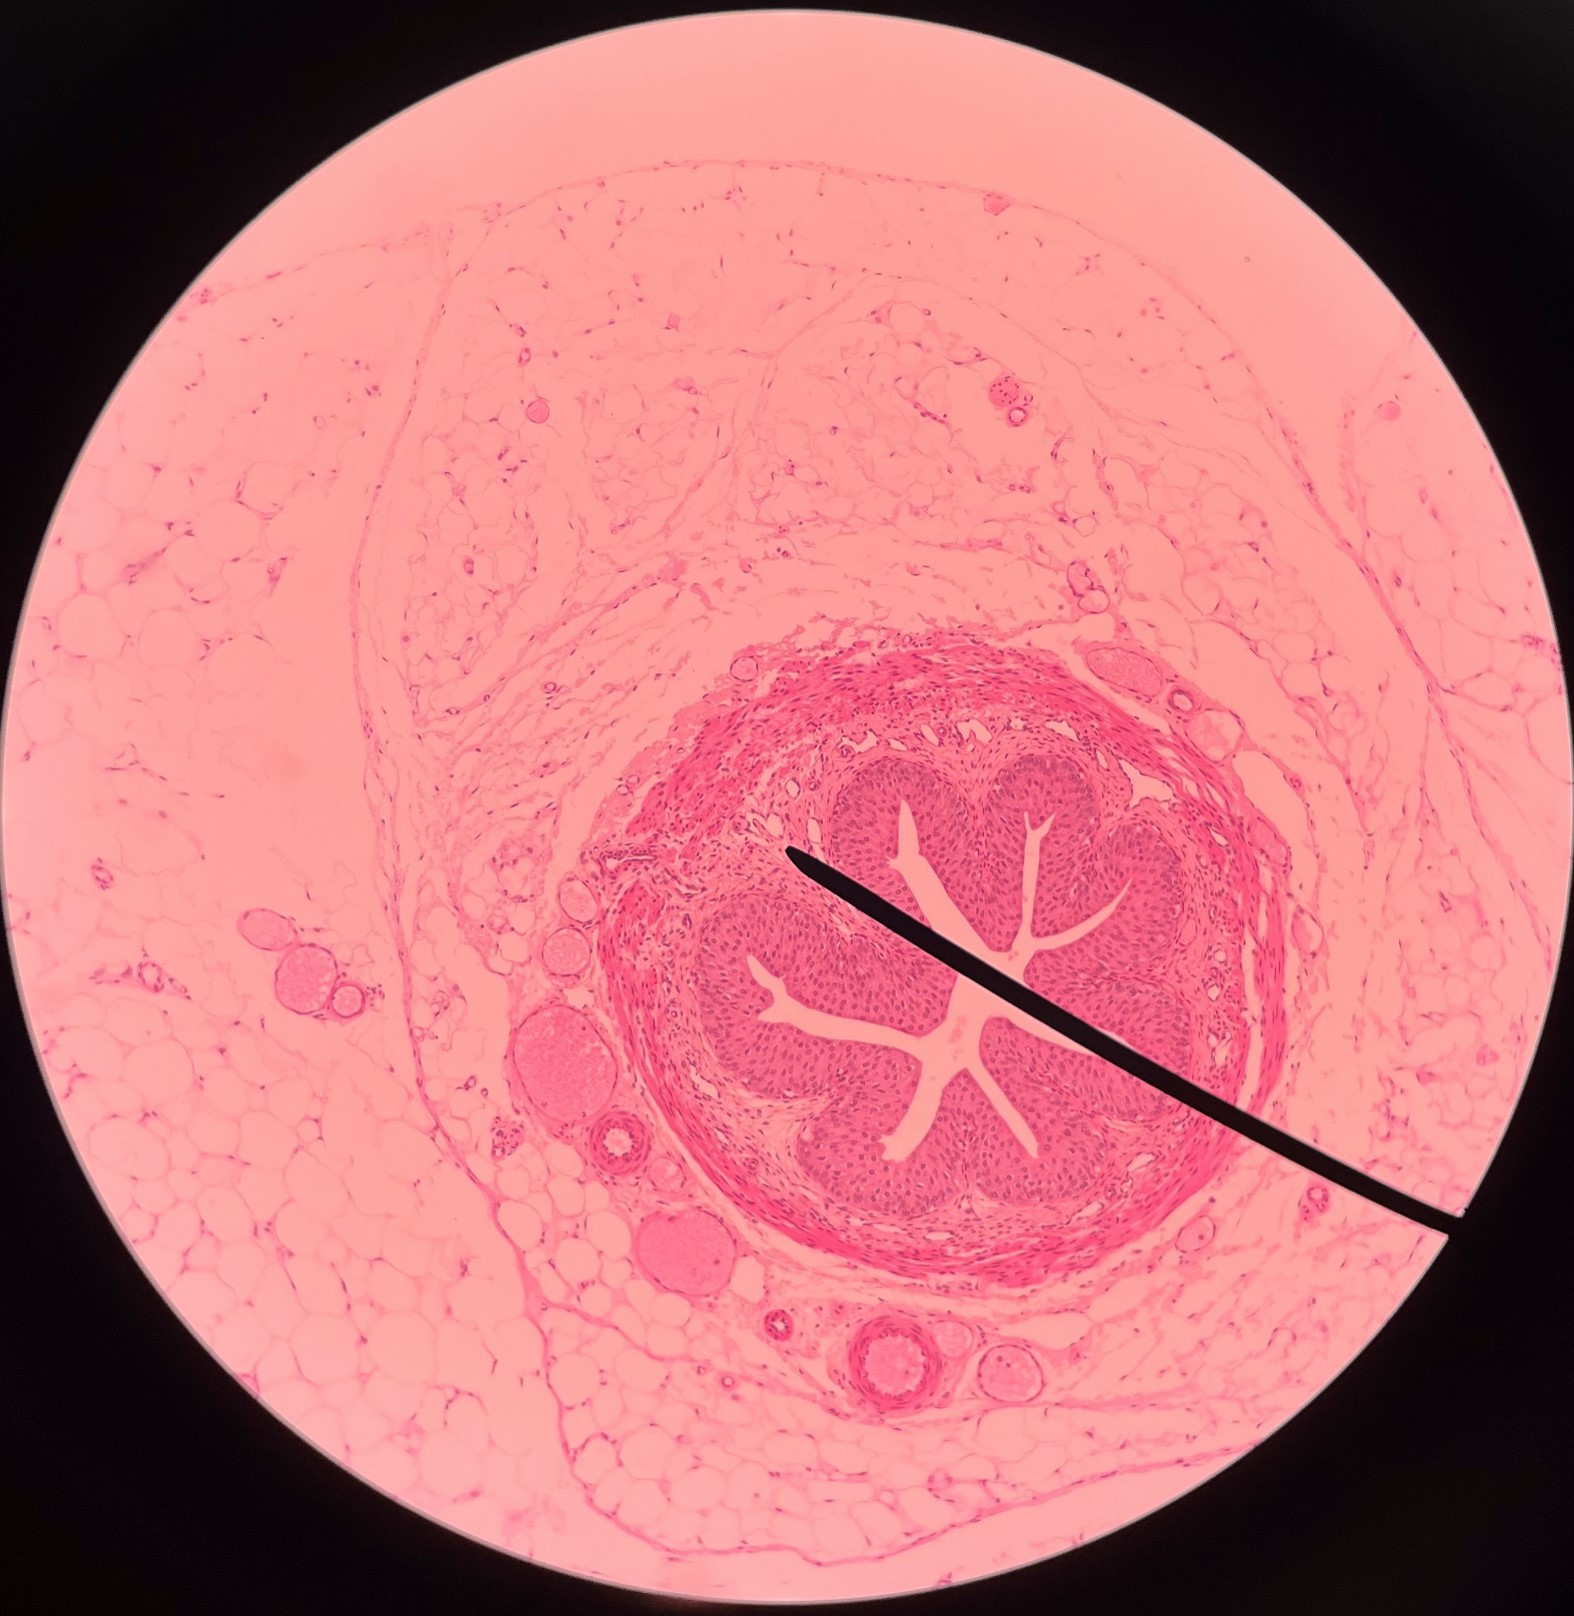

New cards

adventitia

• Slide histology of the ureter.

• The outermost layer of the ureter.

• Composed of connective tissue.

• Superficial to the circular layer of the muscularis.

• The outermost layer of the ureter.

• Composed of connective tissue.

• Superficial to the circular layer of the muscularis.

23

New cards

circular layer of muscularis

• Slide histology of the ureter.

• A smooth muscle layer of the ureter.

• Superficial to the longitudinal layer of the muscularis and deep to the adventitia.

• A smooth muscle layer of the ureter.

• Superficial to the longitudinal layer of the muscularis and deep to the adventitia.

24

New cards

longitudinal layer of muscularis

• Slide histology of the ureter.

• A smooth muscle layer of the ureter.

• Superficial to the mucosa and deep to the circular layer of the muscularis.

• A smooth muscle layer of the ureter.

• Superficial to the mucosa and deep to the circular layer of the muscularis.

25

New cards

mucosa

• Slide histology of the ureter.

• The innermost layer of the ureter.

• Composed of urothelium.

• Faces the lumen of the ureter and is deep to the longitudinal layer of the muscularis.

• The innermost layer of the ureter.

• Composed of urothelium.

• Faces the lumen of the ureter and is deep to the longitudinal layer of the muscularis.